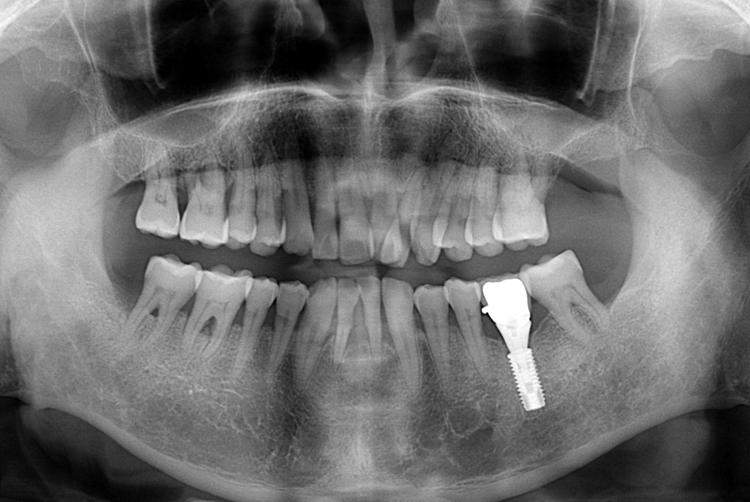

[임플란트] 어금니 임플란트

치료전 : 2016-03-21